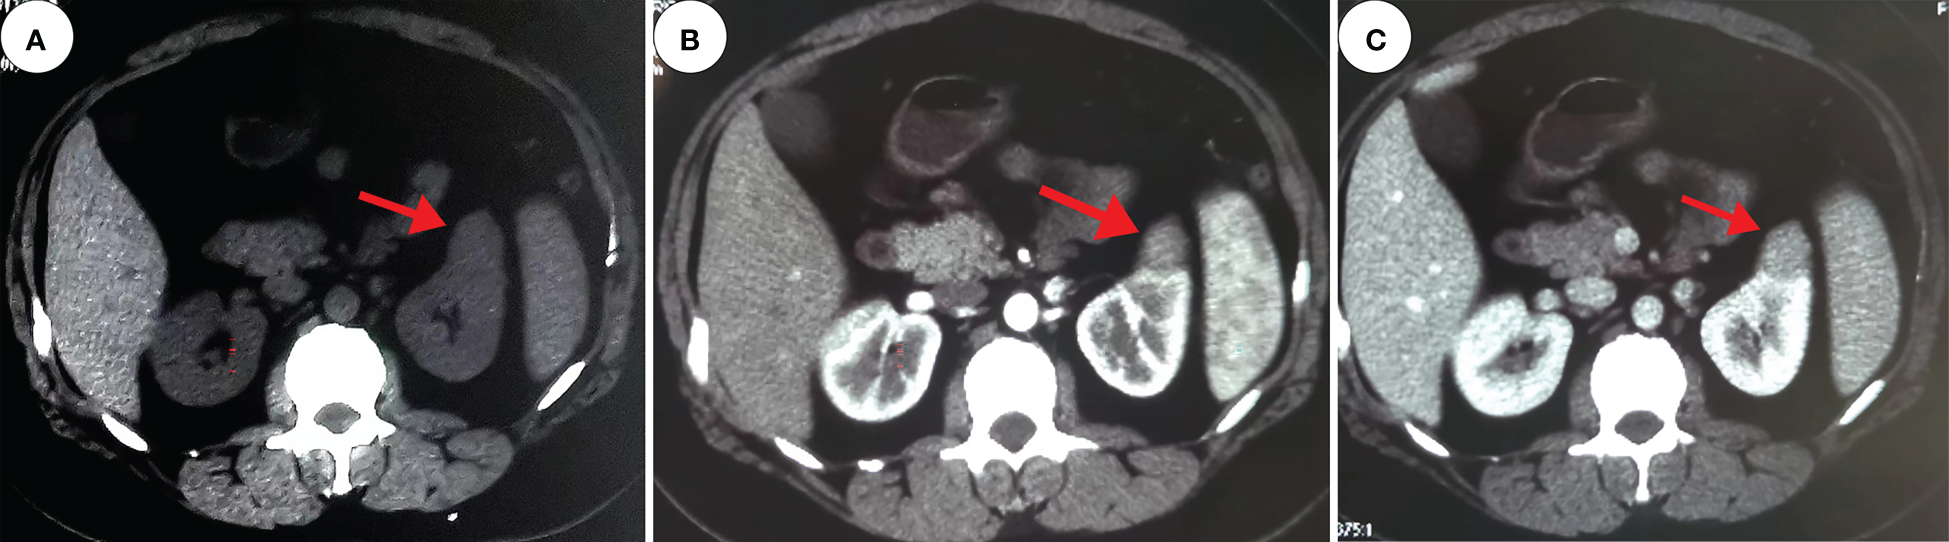

A 30-year-old female patient was admitted to the hospital with a left renal mass found on physical examination. During the course of the disease, there was no low back pain, haematuria, frequent urination and pain, dizziness, palpitations, fever or chills. The patient had not received any specific treatment previously and followed a healthy diet and lifestyle and had no family history of the disease or similar diseases. The patient’s vital signs were normal. There was no swelling, tenderness or pain induced by tapping over either kidney area. Urological ultrasound showed a moderate echogenic mass of approximately 2.6 cm×2.3 cm in the middle and upper parts of the left kidney, with a clear boundary and regular shape and no blood flow signal (Figure 1). Chest CT showed no abnormalities. Abdominal CT showed a left renal mass, and renal clear cell carcinoma was considered (Figure 2). The preoperative diagnosis was a left renal mass, and the patient underwent laparoscopic partial left nephrectomy. The tumour capsule was intact in the resected specimen, and brown fish-like tissue was observed after a longitudinal incision of the tumour. Histopathological studies of the resected tumour revealed the tumour was well demarcated and had a complex branched papillary structure with a fibrous vascular axis, and the papillary surface was covered with a monolayer of cuboidal or columnar cells, with eosinophilic cytoplasm and characteristic nuclei located at the top of the cytoplasm away from the basement membrane (Figures 3A, B). Immunohistochemical studies of the tumour showed that the lesion was positive for the expression of GATA3, KRT7, p504s, EMA, PAX-2, PAX-8, SHDB, Ki-67 and TTF-1 and negative for vimentin, CD5, CD10, WT-1, CAIX, TFE-3, HMB-45, CD117, ALK and TG (Figures 3C, D). Histomorphology and immunophenotype were consistent with papillary renal neoplasm with reverse polarity. The patient declined further molecular genetic testing for financial reasons. The patient did not receive any treatment for 7 months after the operation, and there was no recurrence or metastasis.

Figure 2

Computed tomography. These images show a 2.4 cm×2.2 cm equal-density mass in the anterior upper part of the left kidney, with poorly defined margins and a calcium density shadow in the mass [(A), red arrow]. The enhancement scan shows inhomogeneous enhancement [(B, C), red arrow].